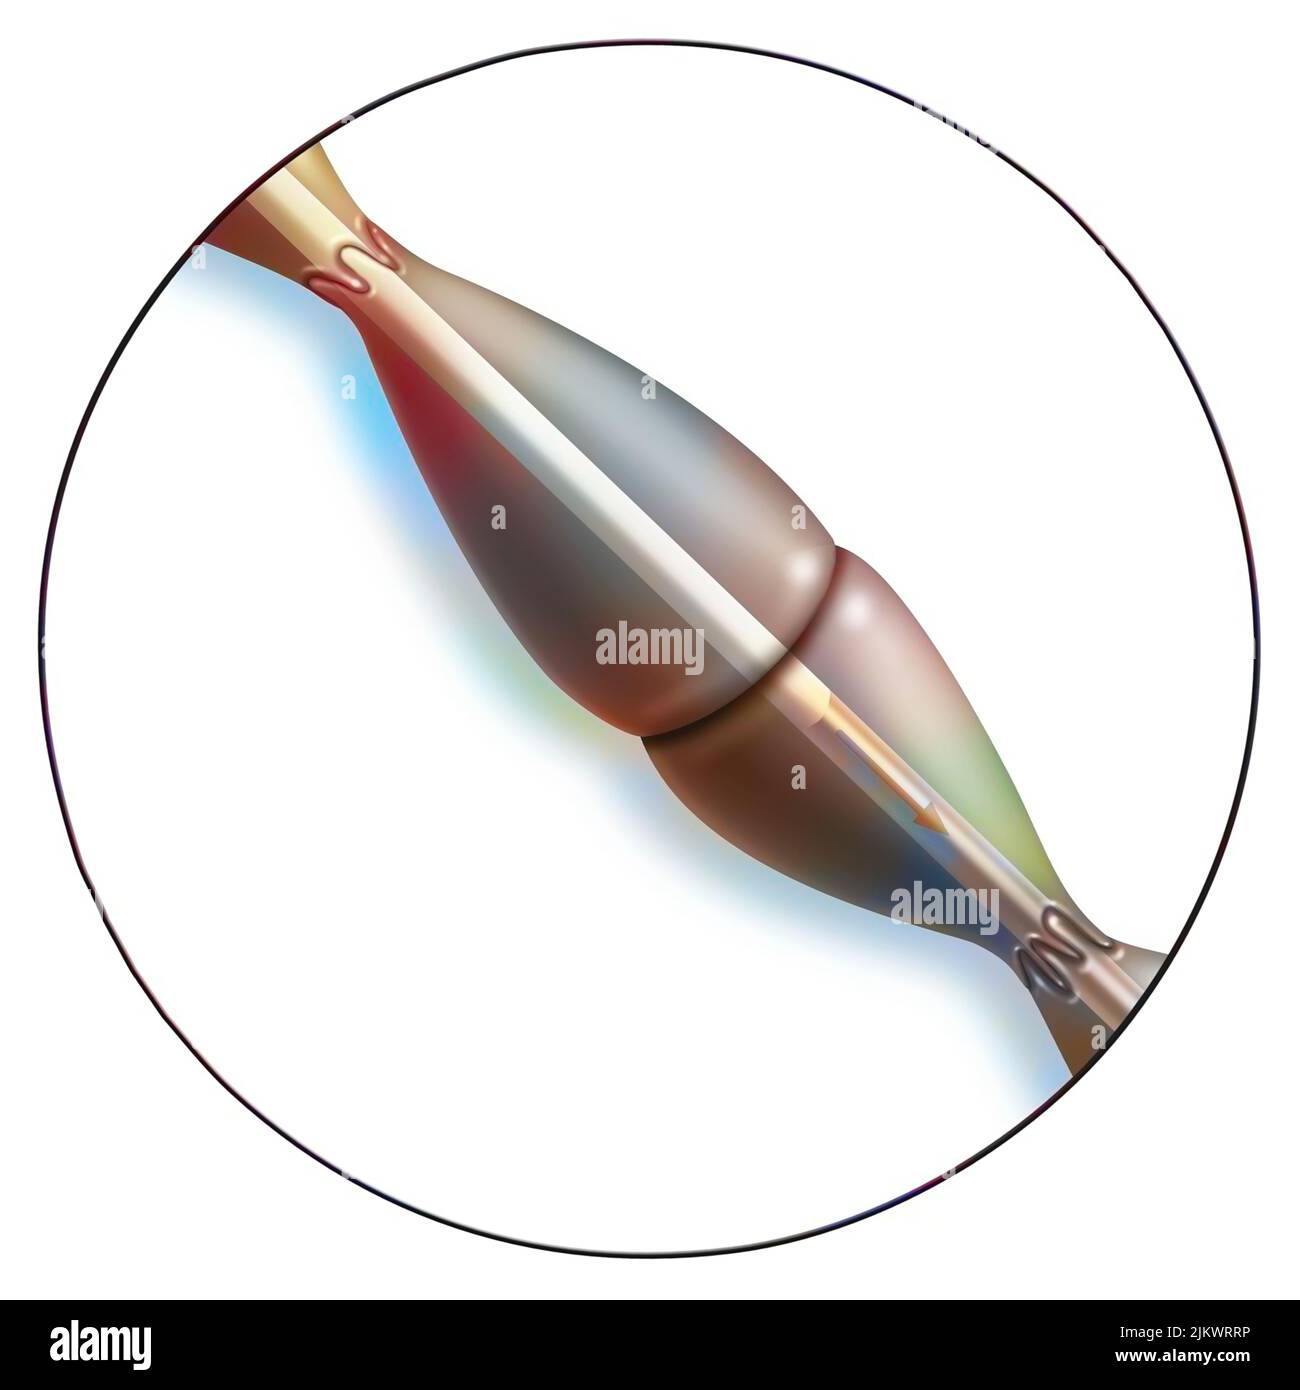

RF2JKWMRF–Myofibrill contracté, composé de myofilaments et de protéines, permettant la contraction musculaire.